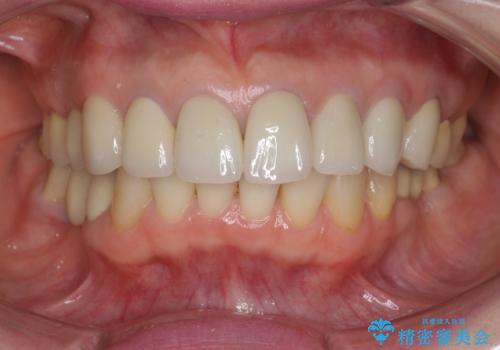

前歯の突き上げを改善する インビザライン による小矯正

- 下顎前歯のガタつきにより上顎前歯のクラウンに突き上げ・動揺が認められ、また歯ぎしりもあることから下顎前歯のみの小矯正をインビザライン で行うこととなりました。

- 5ヶ月